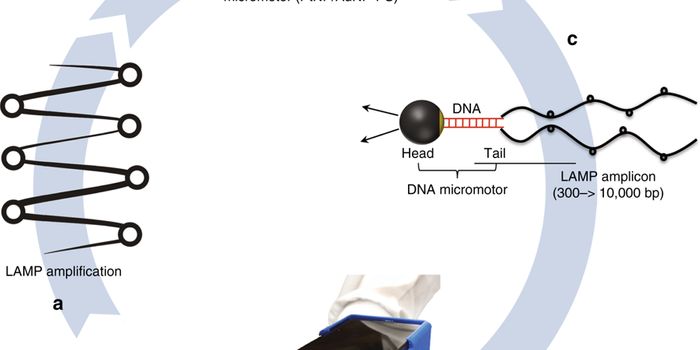

JUN 29, 2021ImmunologyAmid the widespread outbreak of the COVID-19 caused by SARS-CoV-2, the development of test methods that can efficiently ...